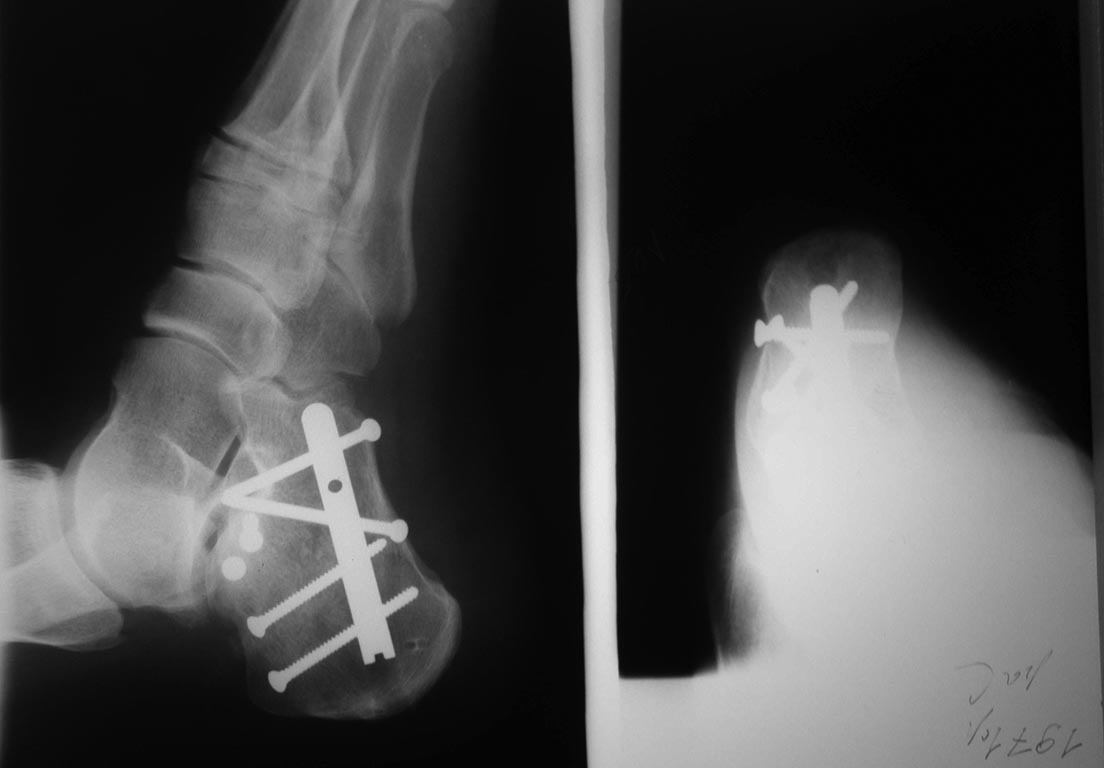

Во вложении фото снимков пациента на всех этапах лечения.

Остеосинтез мы выполняем либо винтами, либо аппаратом собственной конструкции. Выбор этих способов остеосинтеза был обусловлен их доступностью и эффективностью. Оба фиксатора присутствуют в операционной в любое время.

Аппарат аксиальной фиксации позволяет нашим пациентам передвигаться с опорой в спецобуви и рано восстанавливать функцию смежных суставов. Аппрарат функционирует на принципе педнапряженной арочной конструкции в котором два пучка спиц, проведенных аксиально наряжены по отношению друг к другу о точки опоры на пяточной кости.

Остеосинтез выполняем аппаратом аксиальной фиксации(комплектуется из делалей аппарата Илизарова) или винтами. Обе методики остеосинтеза просты, надежны и доступны для любого травматологического отделения.И в экстренном поряжке - так же доступны.

Аппарат аксиальной фиксации позвлляет раннюю нагрузку(особенно важно при двусторонних переломах пяточных костей и переломов контрлатеральной конечности) и восстановление объема движений. Осложнения минимальные.